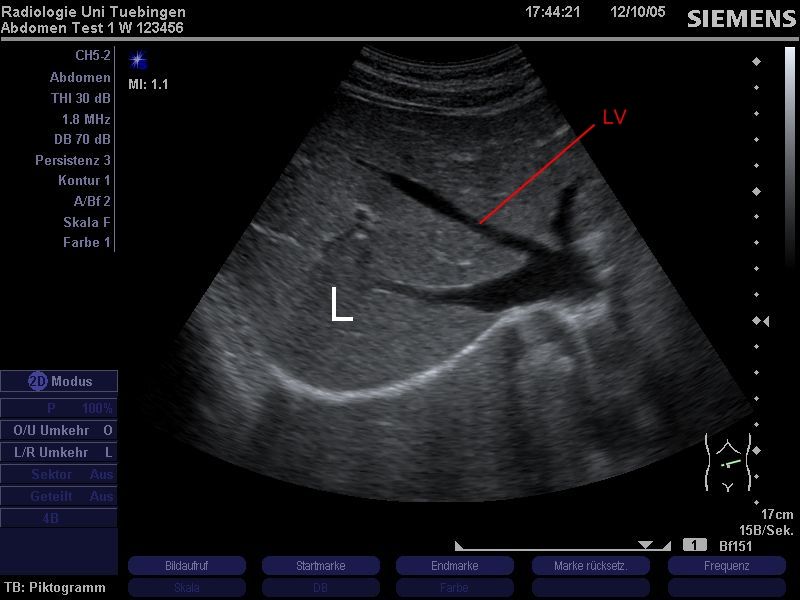

Oberbauchquerschnitt.

Regelrechte Darstellung des Leberparenchyms (=Lebergewebe) sowie der Lebergefäße (Lebervenenstern)